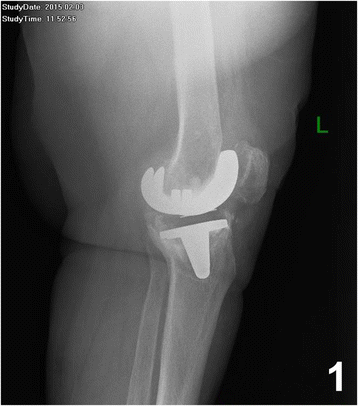

In 2004 a 69 year old woman underwent total left knee replacement with a cemented knee endoprosthesis for osteoarthritis. In February 2015 a loosening of the prosthesis was diagnosed radiologically (Fig. 1) in association with a rupture of the collateral ligament.